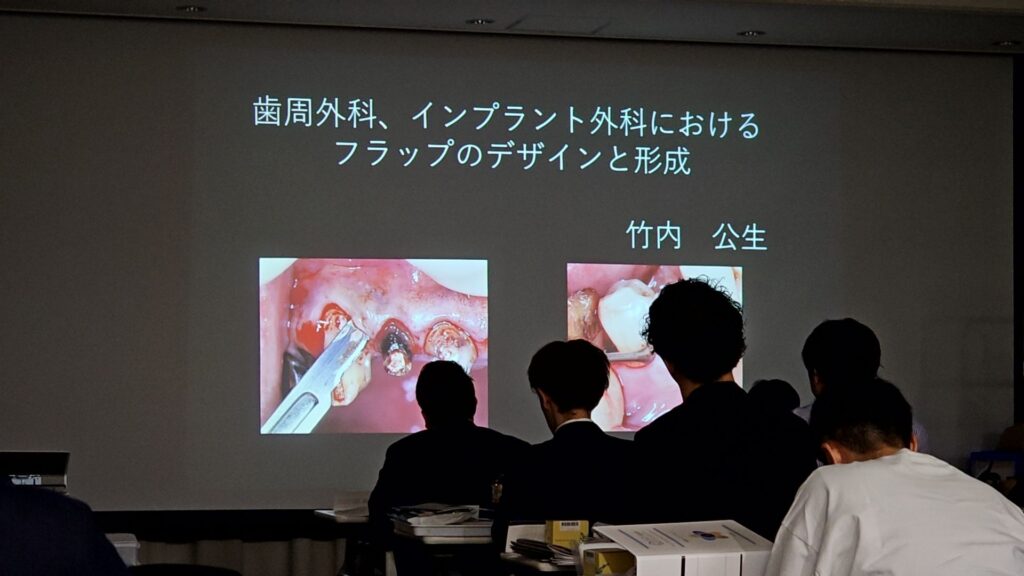

また、竹内先生の症例の写真解説と動画を見た後に歯周外科手術の実習を模型を使って行ないました!

使ったことのない器具の解説と実際に使わせて貰って実習ができるので、使用した感覚や便利な点なども体感できたため、とても面白かったです(*^^*)